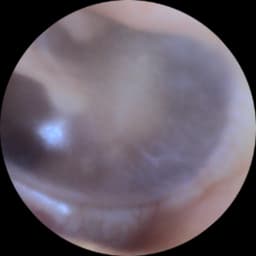

A small camera will assess your membrane health and ear canal. This is a quick painless procedure pictures can be forwarded to your Gp if necessary. Please note we understand if you need to cancel, but a no show you will be charged £25 .Please let us know within 24hrs of your allocated time . PLEASE NOTE THIS IS FREE AND IGNORE IF THE SYSTEM ASKS YOU TO PAY A DEPOSIT!!!I We are trying g to fix this error .